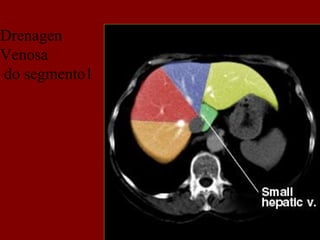

Drenagen

Venosa

do segmento1